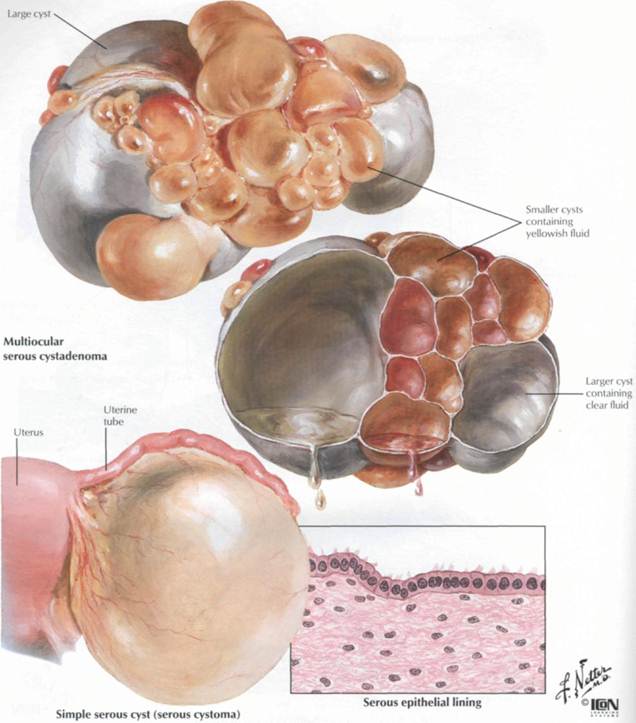

Гистологические изображения фолликулярной кисты яичника